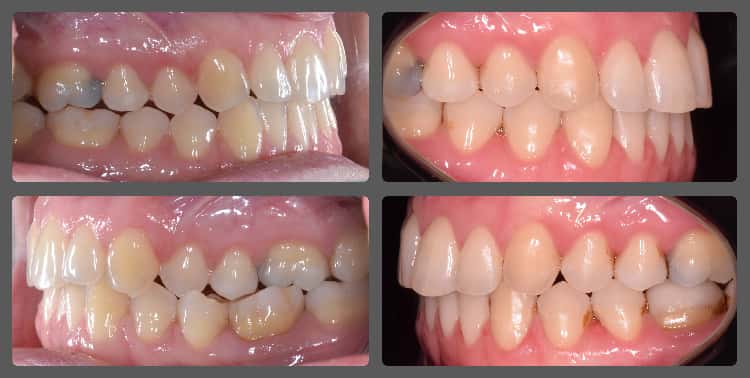

Zoli torlódott alsó fogai miatt szeretett volna fogszabályozó készüléket. Régebben 2 db felső kisőrlő fog eltávolításával már fogszabályozták, azonban az alsó fogív eltérései jelentősek voltak. A torlódás mellé közepes mértékű mélyharapás társult, valamint a bal oldali kisőrlő fogaknál non-occlusiot figyeltem meg. Ez azt jelenti, hogy esetünkben a felső első kisőrlő fog az alsó első és második kisőrlő fog közé, de azok külső felszínére harap. Ez a felső fogat kifelé, az alsókat befelé, a nyelv felé dönti és hosszútávon súlyos elváltozást okoz. Alsó-felső Pitts21 rögzített fogszabályzóval, intermaxilláris gumihúzással, harapásemelőkkel és tolórugókkal Zoli fogait nagyon gyorsan, 13 hónap alatt sikerült tökéletes pozícióba szabályoznunk, mind esztétikai, mind funkcionális szempontból (persze ehhez kellett a töretlen lelkesedése, együttműködése is). A kezelés végén az alsó fogívre fix retainert helyeztem fel az elért állapot megőrzésére. A végeredmény úgy gondolom mindent elmond!